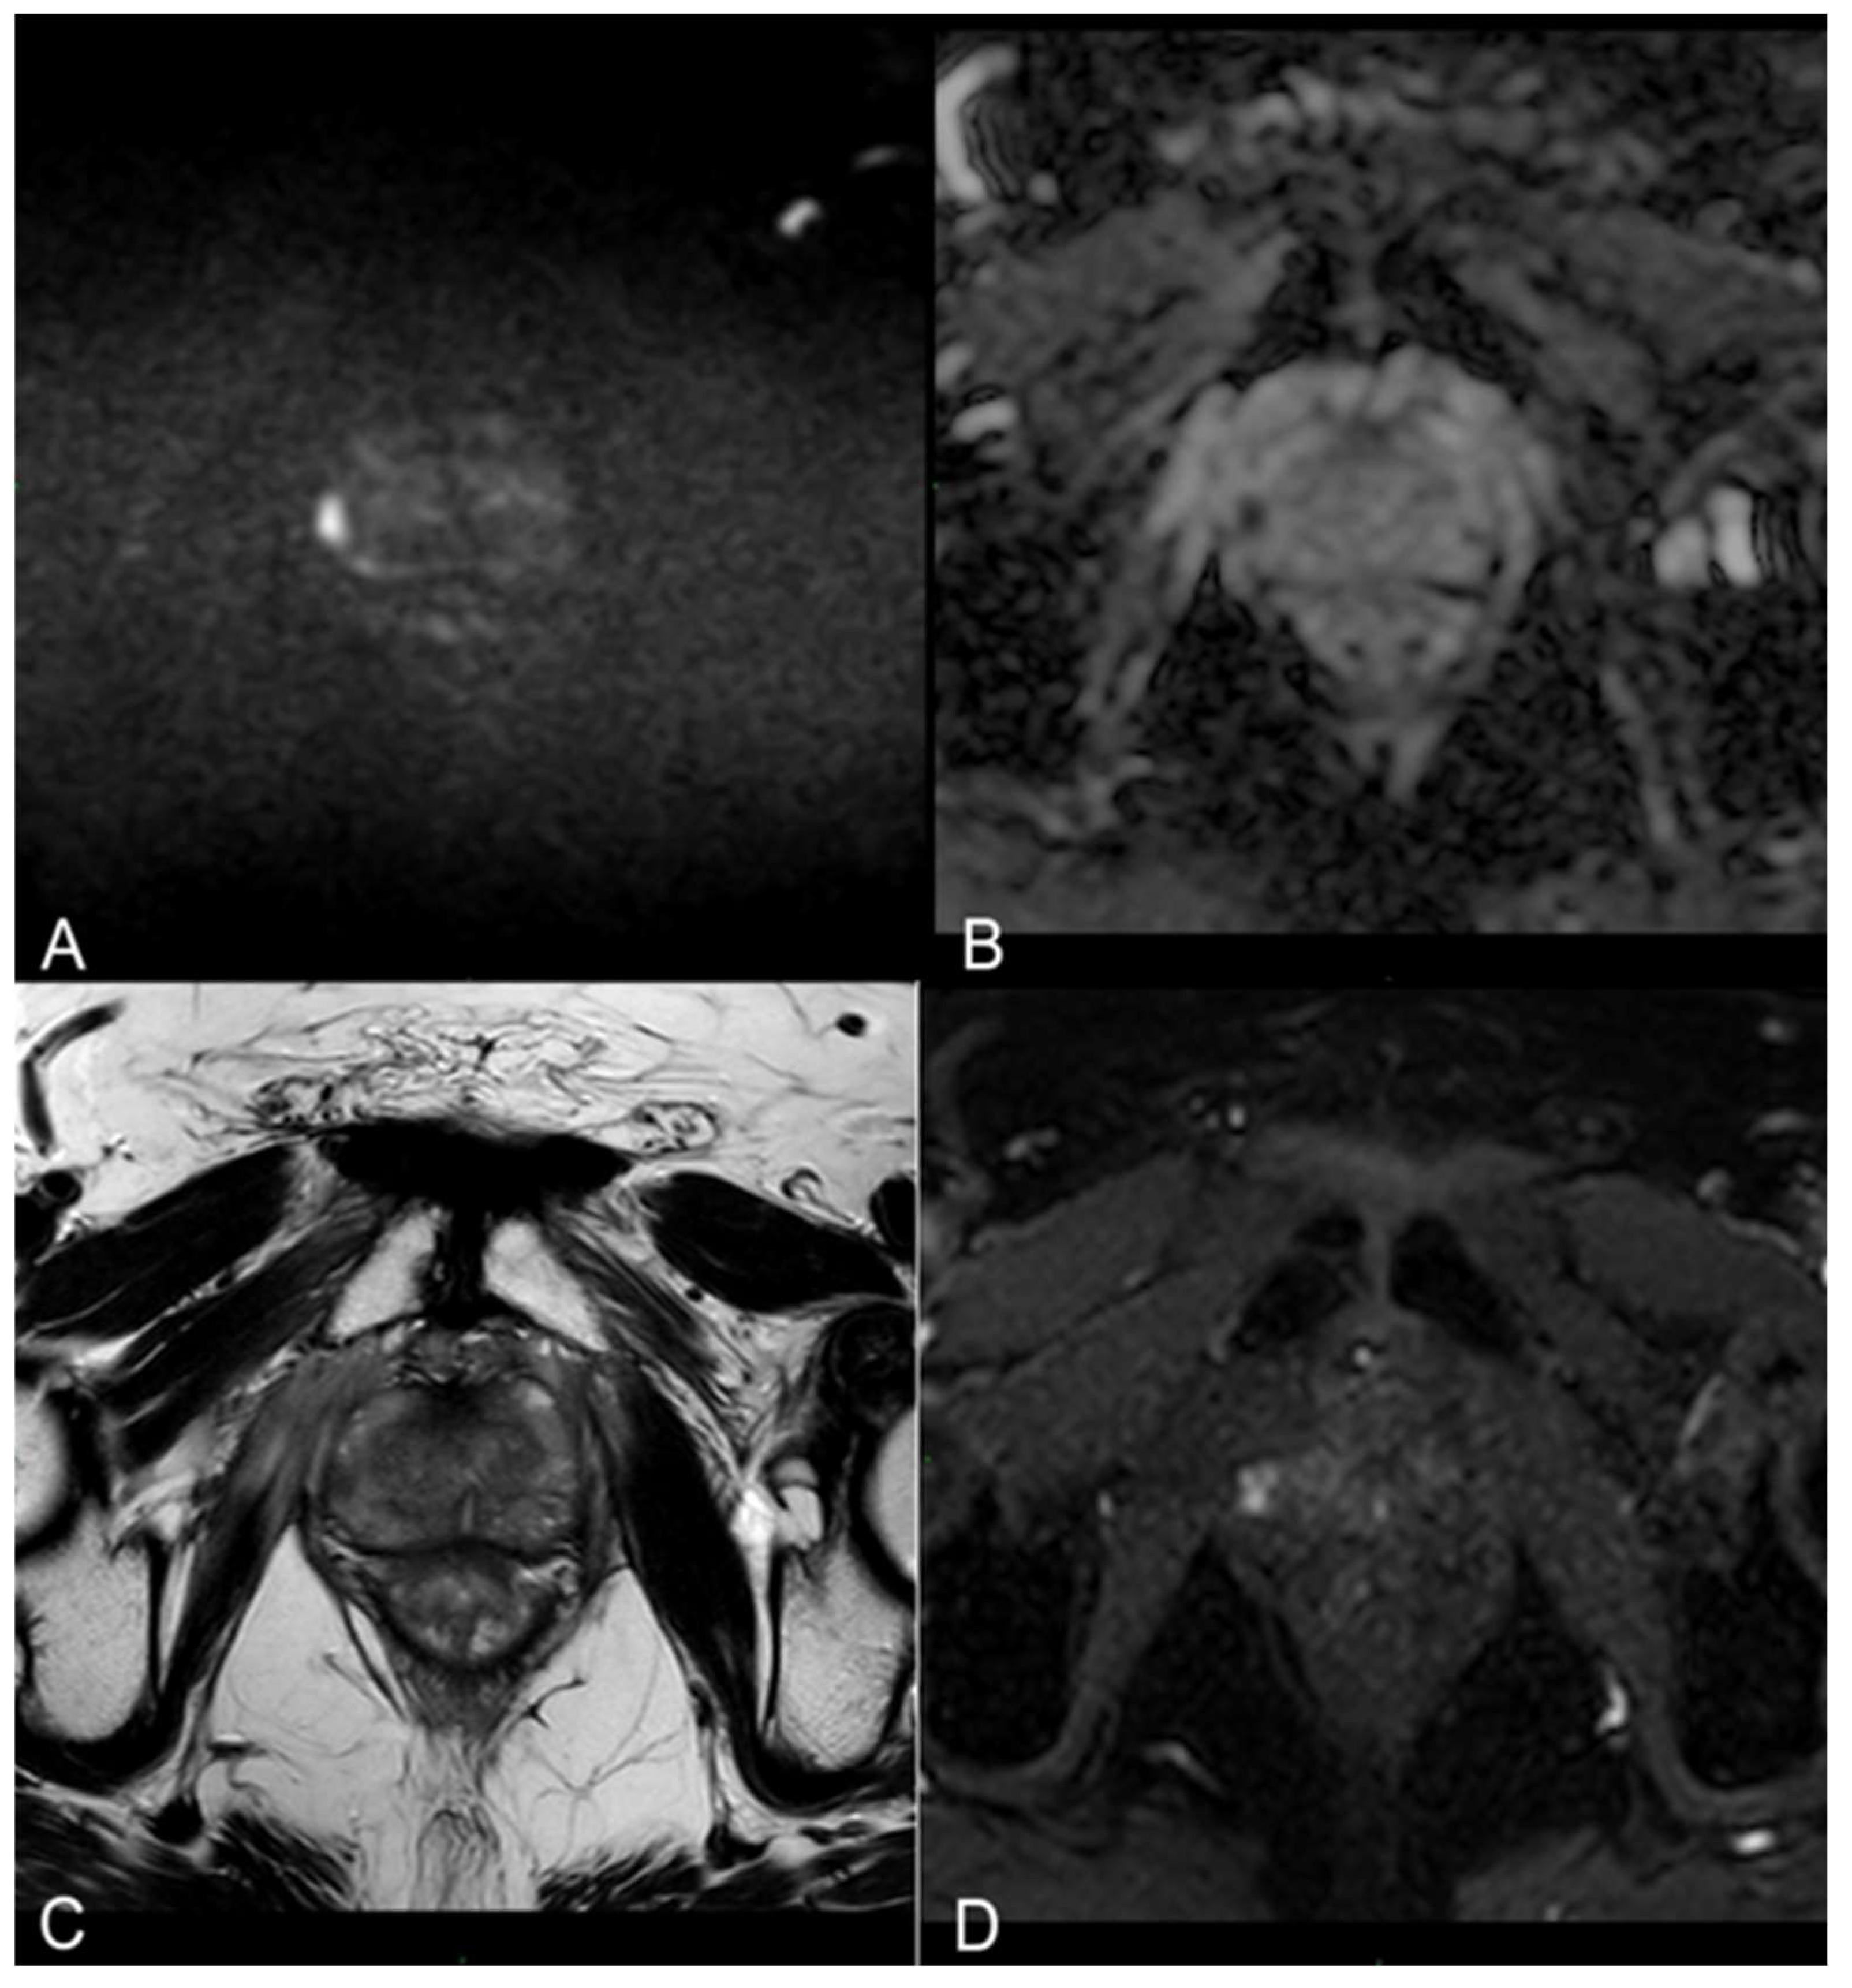

The pre-procedural evaluation consisted of an electrocardiogram, complete blood count, urine examination and urine culture, and evaluation of post-voiding residue and uroflowmetry. Patients were also submitted to IPSS-QoL and IIEF-5 questionnaires at baseline and during follow-up to investigate any procedure-related erectile dysfunction or urinary symptoms. Given that the procedure was guided by MRI/US fusion images, a 3T multiparametric prostate resonance (mpMRI) scan was performed for each patient at Time 0, adhering to the protocol delineated in Supplementary Table S1 (refer also to Figure 1).

Figure 1.

(A,B) Diffusion-weighted imaging (DWI) b-value 2500 s/mm2 and ADC map on axial plane showing focal marked hyperintensity on high b-value DWI sequences corresponding to a hypointensity on the ADC map (PI-RADS 4). (C) T2-weighted TSE sequence on axial plane showing a hypointense lesion in the peripheral zone of the right middle portion of the gland. A curvilinear contact surface with the prostate capsule is demonstrated without any sign of capsule invasion. (D) Dynamic Contrast-Enhanced Imaging (DCE) with T1-weighted Dixon sequence with fat suppression on axial plane: early and significant focal enhancement in the peripheral zone of the right mid-portion of the gland.